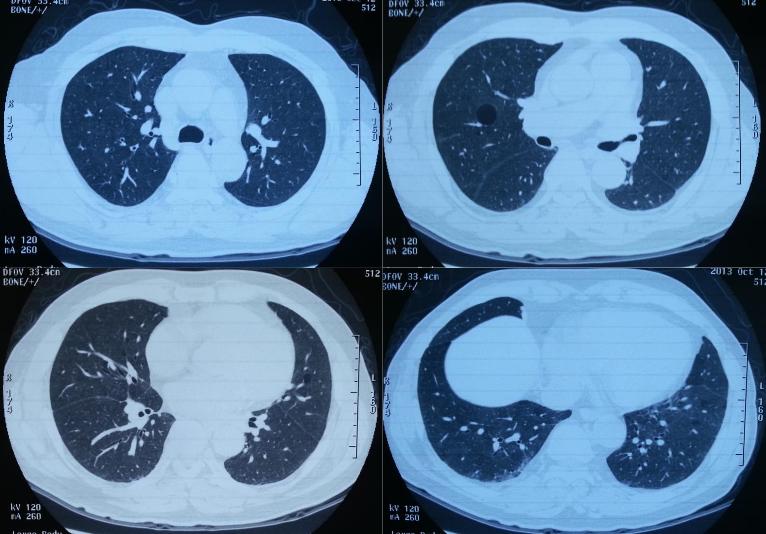

2013年10月为明确诊断,就诊北京朝阳医院。那时患者没有太多症状,FVC 3.26L(84.8%),FEV1/FVC 81.8%,Dlco 5.88(68.3%)。HRCT提示间质性肺炎(轻),细支气管炎,肺大疱。但是没有获得之前诊断为肺炎或间质性肺炎的CT。

影像资料如下:

2012-2-16,在当地诊断为间质性肺炎;2012-3-29,病灶吸收;2013年10月,病灶较前明显吸收;2015-5-22,病灶加重;2015-5-29(一个星期后)病灶又有所吸收。